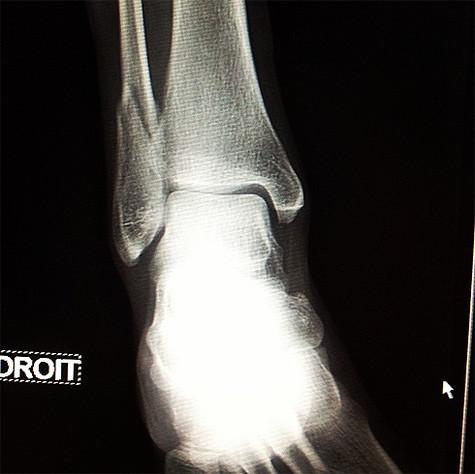

Известная актриса и Рената Литвинова поделилась печальной – сломала ногу в падения. В с этим спектакли артистки на следующий месяц отменены.

«К сожалению, спектакли на месяц отменены - поскользнулась, - перелом. Так обидно», - Рената в своем микроблоге, рентгеновский снимок перелома.

Рентгеновский ноги Ренаты Литвиновой. Фото: Twitter.com.